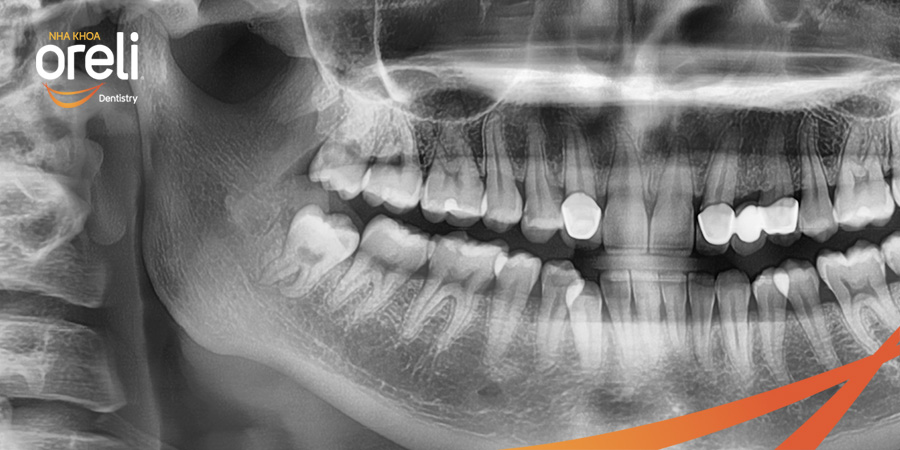

Nhổ răng khôn hàm dưới khó do mọc ngang – Case tại Oreli

Nhổ răng khôn

Mọc lệch

Xem thêm